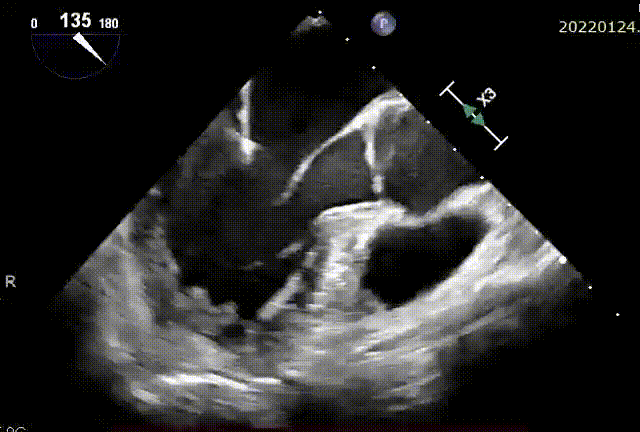

术毕二尖瓣反流消失

患者全麻后,在左胸心尖对应处胸壁切开4cm微小切口,随即在经食道超声引导下,使用E-Chord®二尖瓣修复装置在P2-P3区域成功植入三对人工腱索并固定在心尖,二尖瓣反流立刻完全消失。手术全程约1小时,其中心内操作时间仅20分钟,可谓行云流水、一气呵成。手术无需体外循环、无需心脏停跳、无需心脏切开,E-Chord®系统直径只有 3mm(9F),是全球最细的二尖瓣修复装置,创伤极小,几乎无出血。手术在完全超声引导下进行,不但定位精确,且无任何放射线,堪称“绿色介入手术”。

术后患者恢复顺利,原有胸闷气喘、不能平卧等症状消失,术后第二天(40小时)即出院回家。